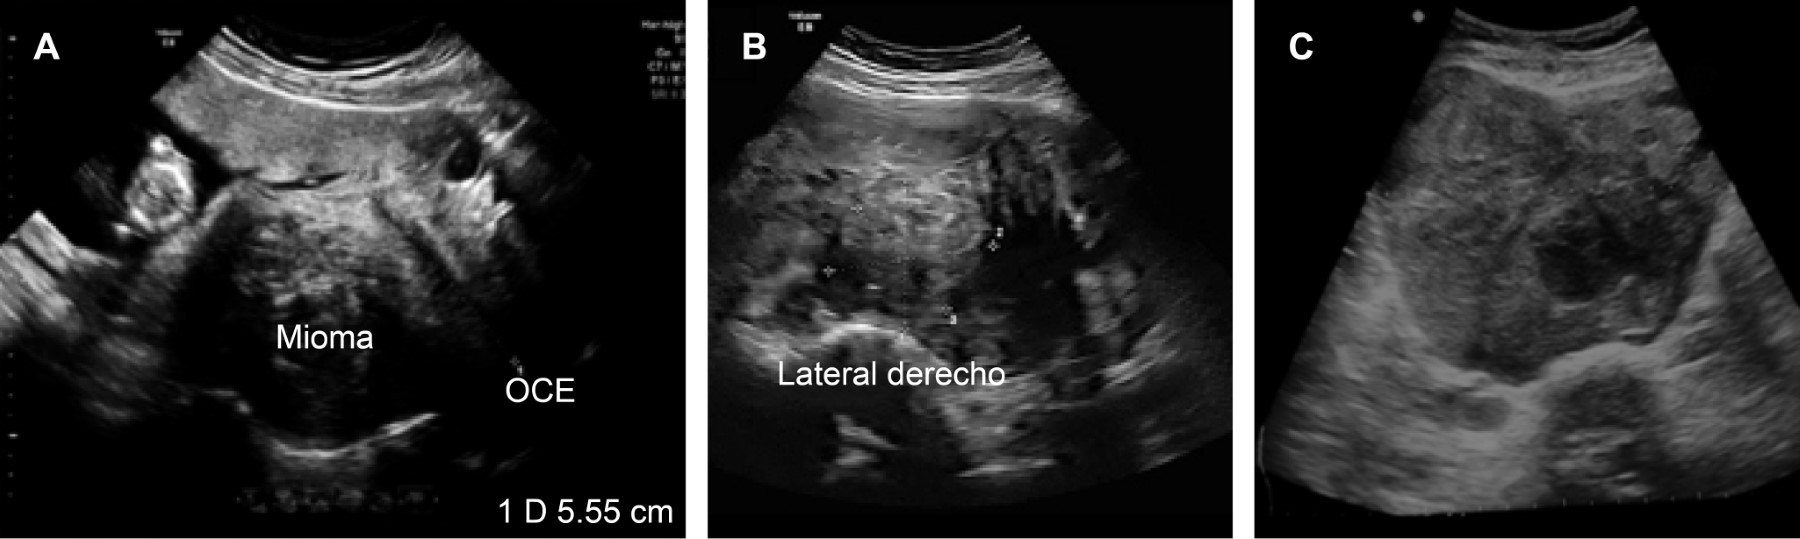

Se realiza ultrasonido pélvico que reporta tumoración sólida uterina de ecogenicidad heterogénea que mide 13.4 × 13.1 × 12.5 cm, con áreas de degeneración quística, sugiriendo miomatosis intramural de grandes elementos (Figura 1).

Figura 1